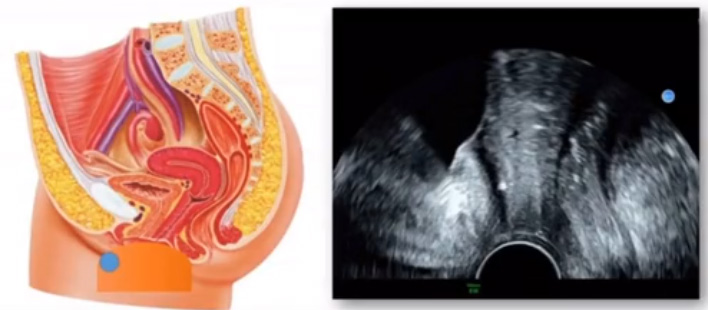

位于輸卵管的后下方,子宮兩側的后上方;借卵巢系膜與子宮闊韌帶后層相連。正常成人卵巢約4x3x2cm,跟睪丸的數值差不多,都是性器官,絕經后卵巢萎縮變小、變硬。所以絕經后婦女很難找到卵巢,主要功能:生殖和內分泌功能分泌性激素。女性的第二性征。女性內生殖器的血管分布,動脈有子宮動脈,卵巢動脈,陰道動脈,陰部內動脈。靜脈它是與動脈伴行。重要了解的是子宮動脈,子宮動脈是髂內動脈前干的重要分支,妊娠時候血流速度會增加的,為無創性檢查胎盤血管阻力的方法。未孕期頻譜為高阻力低舒張波形;正常妊娠時血流速度增加,血流阻力下降。